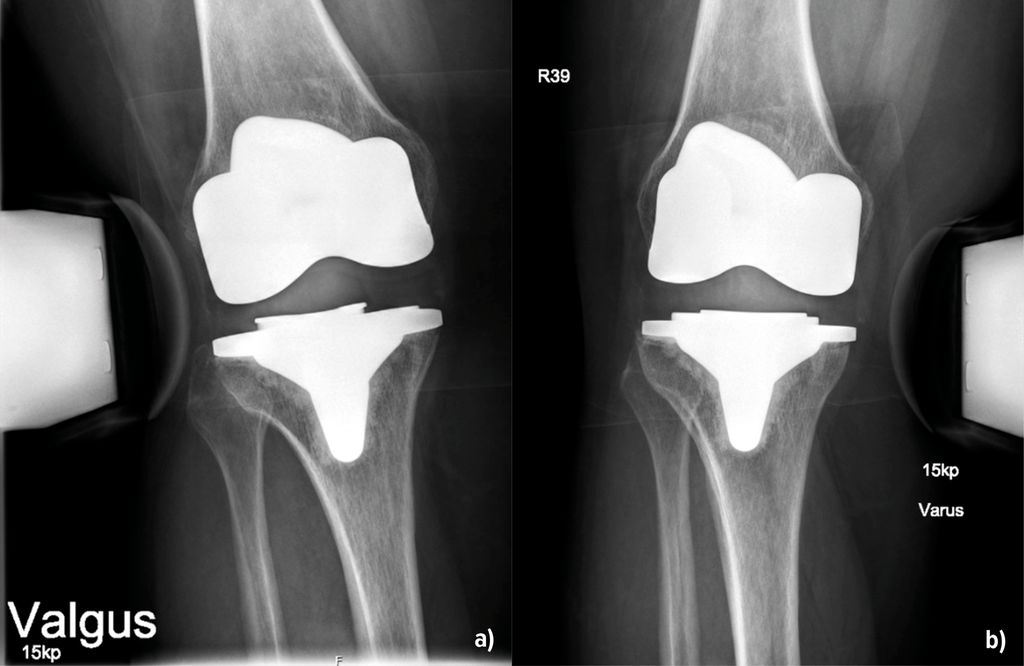

Abb. 1:Instabilität infolge eines Verschleisses. Im ap. Röntgenbild (a) sind die vermehrte laterale Aufklappbarkeit und die mediale Verschmälerung des Gelenkspaltes gut sichtbar. Das Inlay weist deutliche Verschleissspuren auf (b). Nach dem Wechsel auf ein neues Inlay in primärer Höhe ist im Röntgenbild der Gelenkspalt wieder gleichmässig dargestellt (c)

Die Instabilität von Knietotalendoprothesen beeinflusst die Zufriedenheit der Patient:innen und führt häufig zu Revisionseingriffen. In einer grossen retrospektiven Studie mit Erfassung von fast 40000 Patient:innen aus den Jahren 1996–2021 konnten Ergin et al. (2025) Risikofaktoren, welche mit einer Instabilität nach Endoprothetik einhergehen, darstellen. Dazu gehörten ein jüngeres Alter, das weibliche Geschlecht, ein Schlaganfall, tiefe Beinvenenthrombosen, Nickelallergie, Osteoporose und – überraschend – die Sklerodermie. Die Adipositas stellt demnach kein erhöhtes Risiko dar. Über die Details der Ursachen berichtet die Arbeit allerdings nicht, sondern beschreibt diese als multifaktoriell. Jedoch können die Autoren aus der eigenen klinischen Praxis berichten, dass durchaus Unterschiede in Bezug auf das Inlay bestehen. Entweder war dieses primär zu flach oder es ist zu einer Lockerung der Bänder im Verlauf gekommen. Auch der Verschleiss des Inlays über die Zeit spielt erfahrungsgemäss eine Rolle (Abb. 1). Bei der Differenzierung, welches Ausmass einer Varus- oder Valguslaxizität zu einem annehmbaren oder schlechten klinischen Ergebnis führt, fanden Mitsu-Uchi et al. (2025), dass eine mittlere Instabilität von 3–6mm im medialen Kompartiment für ein besseres postoperatives Ergebnis von Bedeutung sei. Eine straffe Implantation mit einer Instabilität von <3mm sowie Instabilitäten von >6mm führten demnach zu niedrigeren Zufriedenheitswerten bzw. Knee-Scores. Somit soll eine mittlere mediale Laxizität für ein besseres postoperatives Ergebnis sorgen, was bereits bei der Implantation Beachtung finden kann. Neben dem klinischen Nachweis ist die gehaltene Röntgenaufnahme geeignet, um den Befund zu verifizieren und zu dokumentieren (Abb.2). Bezüglich der Ursachen für Fehlschläge primärer Knietotalendoprothesen finden sich die Instabilitäten mit einer Häufigkeit von 7% bzw. 4,55% an 3. bzw. 4. Stelle. Vorwiegende Gründe für Revisionen sind hingegen periprothetische Infektionen (22,3% bzw. 47,73%), die aseptische Lockerung (20,5% bzw. 35,23%) und Bewegungseinschränkungen (5,68%) (Datta et al. 2025, Mozella et al. 2024). In einer Arbeit von Poilvache et al. (2025) wurde das Übergewicht als Risikofaktor für Komplikationen nach K-TEP untersucht. Die Hauptursachen für die initiale Revision waren die aseptische Lockerung mit 37%, die Instabilität (29%) und der Abrieb oder Osteolysen (13%). Die Arbeit erbrachte ganz klar, dass ein BMI >40kg/m2 tendenziell mit einer Reoperation korrelierte. Allerdings nicht wegen Instabilität, sondern wegen periprothetischer Infektionen, und das auch nicht signifikant. Der BMI als Ursache einer Instabilität nach Revision wurde hier ausgeschlossen. Brown et al. (2025) beschrieben ein erhöhtes Risiko mit Hinblick auf eine Revision als Folge einer Instabilität oder einer Lockerung bei Fällen, in denen die Femurkomponente grösser als die Tibiakomponente war. Die Autoren empfahlen, primär die Wahl der Prothesengrössen zu beachten, um Instabilitäten vorzubeugen. Auf die Infektionsraten und den anterioren Knieschmerz fand sich in dieser Kohorte kein Einfluss.